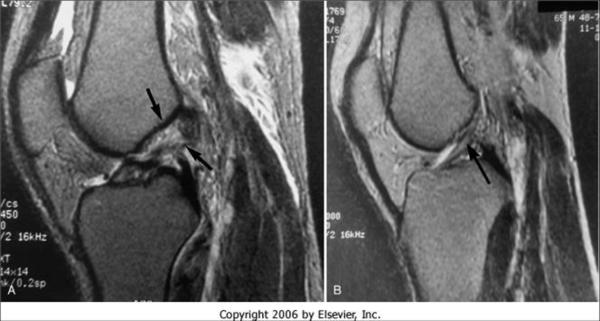

核磁表現(xiàn)

全斷裂

直接征象

1、連續(xù)性中斷(所有層面找不到一個完整的ACL)

2、韌帶增粗呈團塊狀、 ACL內(nèi)形成假瘤,T1WI低信號、T2WI 高低混雜 見不到完整的纖維束。

3、邊緣不規(guī)則、成角扭曲呈波浪狀(MRI連續(xù)性未見中斷、鏡下用探子探察全斷)

4、T2WI彌漫性高信號

間接征象

1 、ACL與脛骨平臺夾角小于45度(松弛)(21%)

2 、外側脛骨平臺、股骨外髁挫傷(對口吻)或骨、軟骨骨折(撕脫骨折)。

3、 PCL角度小于107度, PCL弧度大于0.39

4、 脛骨前移大于7mm

5、外側半月板后移

ACL部分撕裂表現(xiàn)

1、信號增高 T1 T2均可見,仍可見連續(xù)性完整的纖維束

2、 ACL變細

3 、某個序列中見到ACL撕裂的間接征象,而在另一個序列中見到完整的ACL。

慢性損傷

出血、水腫消退,同時由于纖維癖痕的橋接有時可與正常相似,或僅表現(xiàn)為韌帶輪廓、走行的異常(如韌帶的增粗不規(guī)則、成角等,而韌帶信號常無異常)。鄰近組織內(nèi)有無水腫是鑒別急慢性 損傷的主要依據(jù)